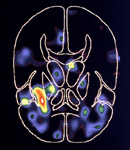

- Si vous vous les répétez mentalement, votre activité cérébrale est probablement proche de l’image de gauche.

- Si vous les visualisez, votre activité cérébrale ressemble plutôt à l’image de droite.

Se répéter les mots Visualiser les mots